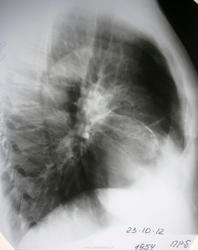

Головоломка ОГК муж 1954 г.р.

Мужчина 1954 г.р. с достаточно выраженной клиникой.

Анамнез : в течении суток стало плохо, выраженная одышка, даложенность в груди, выраженный кашель (длится уже неделю). Скорая заподозрила ТЭЛА, в приемнике поставили пневмонию.

ГЛАВНЫЙ ВОПРОС:  какие есть идеи по поводу кольцевидной тени в проекции нижней доли слева?

боковой снимок правый, т.к. дежурный врач решил что справа пневмония.

Покажите ниже) ... еще ниже))). Что гадать, когда неизвестно, где левый купол и желудок. Обычно такие картинки даёт острое расширение желудка. Или киста. Или еще что. Диафрагму на бочку))

Действительно, похоже на обызвествленную кисту.

А если фиброзный тяж?

булла может

Плевральные наложения.

Мне тоже на ум пришла только обызвествленная киста. НО легочный рисунок-то в пределах "кисты" ничем не отличается от других отделов.

Любовь С., взгляните на боковой.  диафрагма в порядке.

доснял левый бок и стомографировал... оказалась действительно, большая (6х7х5.5 см), кальцинированная полость.

побеседовал с пациентом - курильщик со стажем 45 лет. в детстве припомнил частые обострения бронхита. в 1987 году "что-то там находили, но не помню что; предлагали резать легкое"..

итак, что по-вашему могло оставить после себя такое "яйцо" в легком в 80-х годах?